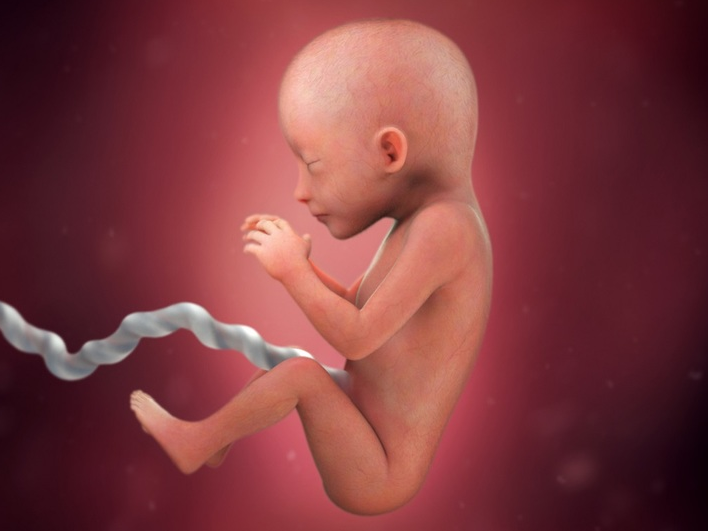

Do đó, khi bé khép chân sẽ cản trở việc xác định giới tính của thai nhi nên không thể dựa trên cách bé khép chân trong hình ảnh siêu âm mà kết luận đó là trai hay gái. Có thể xác định giới tính của thai nhi thông qua siêu âm trong giai đoạn thai kỳ nhất định, thông thường từ tuần thai thứ 18 đến 20 trở đi. Trong quá trình siêu âm, bác sĩ sẽ xác định giới tính là nam hay nữ bằng cách kiểm tra các đặc điểm về giới tính như cấu trúc sinh dục bên trong và ngoài của thai nhi.

Ngày nay, các phương pháp siêu âm hiện đại như siêu âm 4D, siêu âm 5D cho phép bác sĩ có thể dựa vào hình ảnh siêu âm ghi được để phán đoán giới tính của thai nhi dù em bé có khép chân khi siêu âm hay không.

Tình trạng bé khép chân khi siêu âm không cho bác sĩ nhìn thấy giới tính khá phổ biến. Thông thường, nguyên nhân là do tư thế nằm của bé trong tử cung của mẹ. Bé nằm nghiêng một bên với hai chân khép lại với nhau nên che mất bộ phận sinh dục dẫn đến những trường hợp siêu âm nhầm giới tính thai nhi.